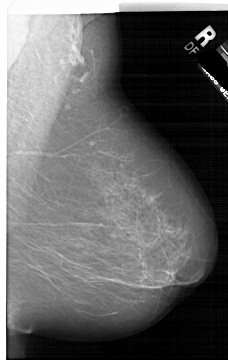

A_1952_1.LEFT_MLO

LEFT_MLO LINES 6391 PIXELS_PER_LINE 4291 BITS_PER_PIXEL 12 RESOLUTION 43.5 OVERLAY